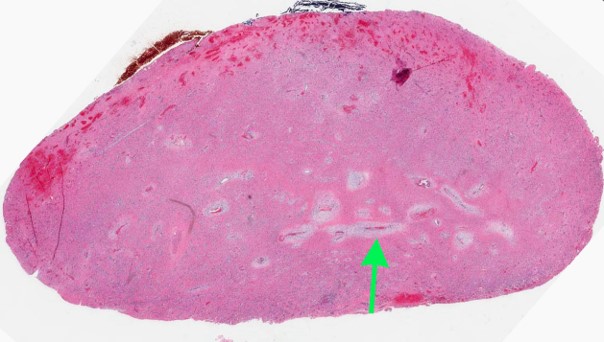

Gross description

- Polypoid firm mass

- Color varies from yellow to dark red or black, depending on the extent of intraoperative hemorrhage

Gross images

Microscopic (histologic) description

Microscopic (histologic) images

Contributed by Bin Xu, M.D., Ph.D.

Contributed by Kelly Magliocca, D.D.S., M.P.H.